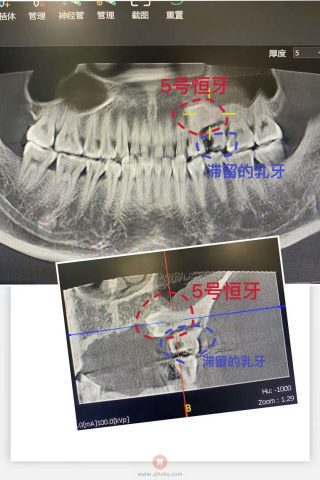

患者管先生乳牙滞留到33岁,拍片显示本该在12周岁左右长出来的恒牙“躺平”横向埋伏在牙床里。